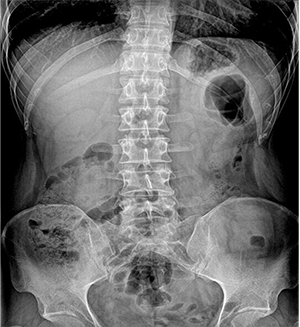

PLD6500系列是普利德研发的医用数字X线摄影机,采用双立柱结构,可供各级医院放射科对头部、胸部、腹部、腰椎、四肢等部位进行立位、卧位、正位、侧位的数字摄影检查。